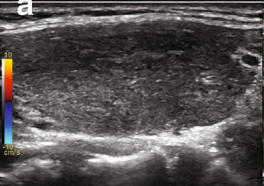

Normal thyroid US appearance

• Homogeneous parenchyma

• Medium-high level echoes (hyperechoic to straps muscles)

• Thin hyperechoic capsule

• Vascular (uniformly distributed)